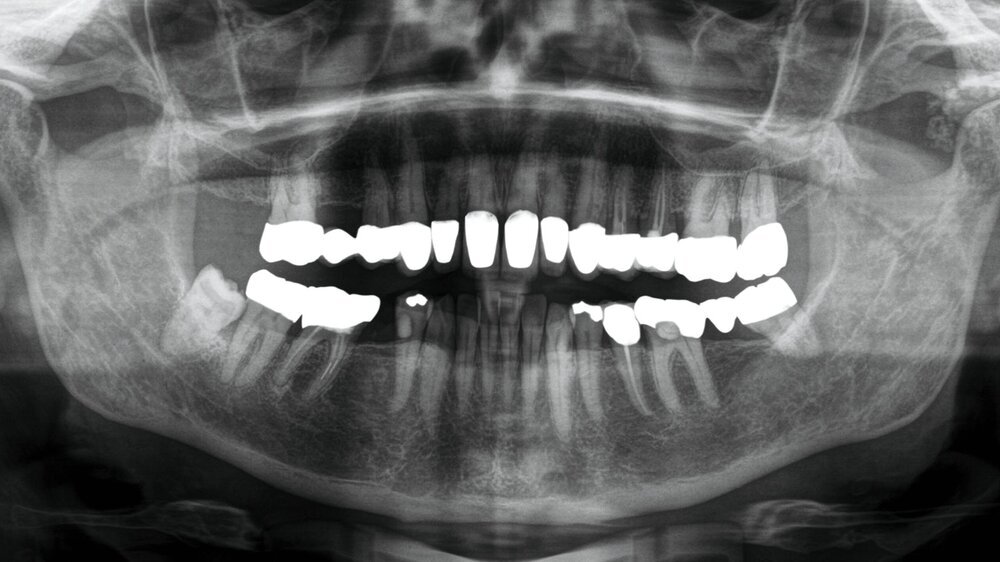

Bei nunmehr erhärteter radiologischer Verdachtsdiagnose auf das Vorliegen einer synovialen Chondromatose erfolgte, entsprechend dem Patientenwunsch, die offen-chirurgische Resektion der multiplen Gelenkkörper in Intubationsnarkose. Der Zugang wurde klassisch präaurikulär mit einer temporalen Extension zum Schutz des Ramus temporalis des Nervi facialis gewählt (Abbildung 3a). Unmittelbar nach Eröffnung der Kiefergelenkkapsel entleerten sich rasch mehrere kleine, knorpelige Raumforderungen (Abbildung 3b), die im Rahmen des Eingriffs vollständig entfernt wurden (Abbildung 3c). Der erweiterte, nun leere obere Gelenkspalt ist in Abbildung 3d dargestellt.

Der histopathologische Befundbericht bestätigte die Verdachtsdiagnose der synovialen Chondromatose – es fanden sich im Präparat mehrere Gewebsfragmente mit reifem Knorpelgewebe und Verkalkungen.